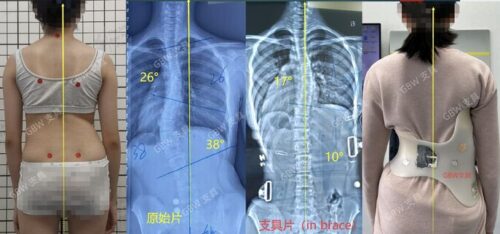

العلاج غير الجراحي: استخدام أحزمة طبية مخصصة وتمارين لتقوية العمود الفقري وزيادة مرونة الحبل الشوكي.

المتابعة المستمرة: تصوير دوري بالأشعة لمراقبة الانحناء ومدى التقدم في العلاج.